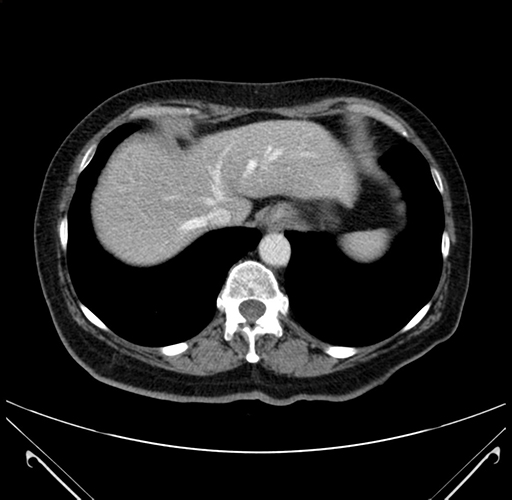

Pre-Chemo: Axial Venous